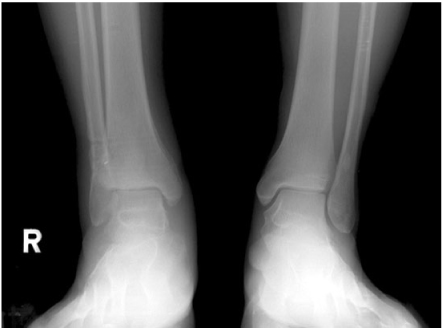

Fig. 8

Follow-up standing ankle radiograph.

Fig. 8 Follow-up standing ankle radiograph.